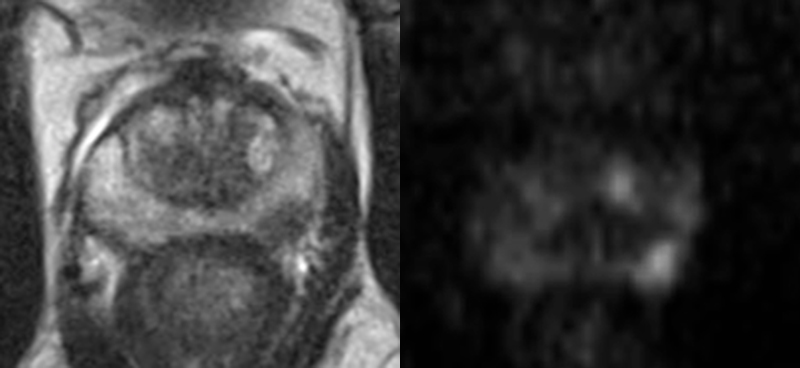

Nyheter Bred övergång till MR-baserad diagnostik följt av enbart riktade biopsier. Det r…